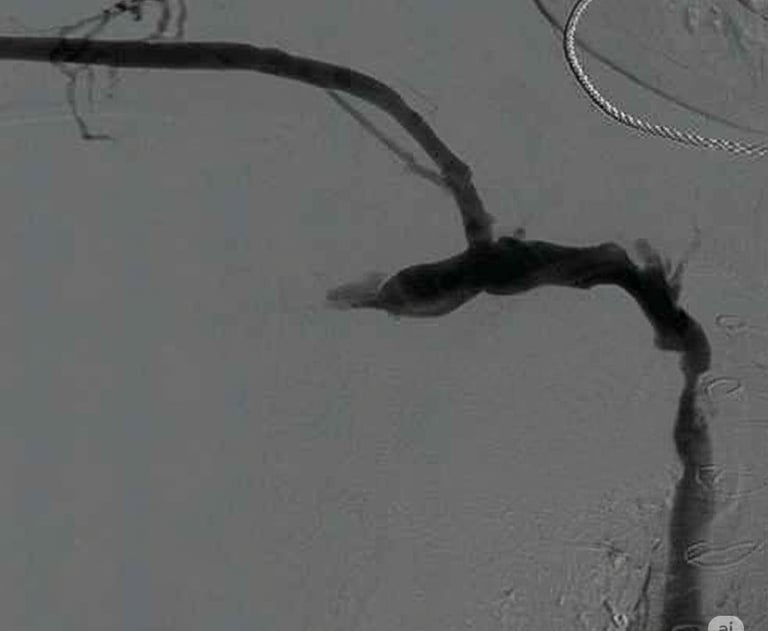

Flebografía de vena cava superior estenótica

Flebografía de la vena ácigos en presencia de estenosis cavoatrial

Estenosis de la vena yugular con dilatación de sus efluentes